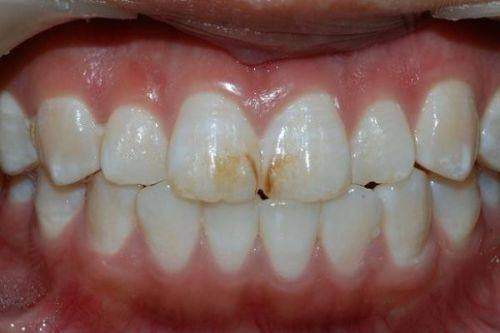

氟斑牙

四环素牙